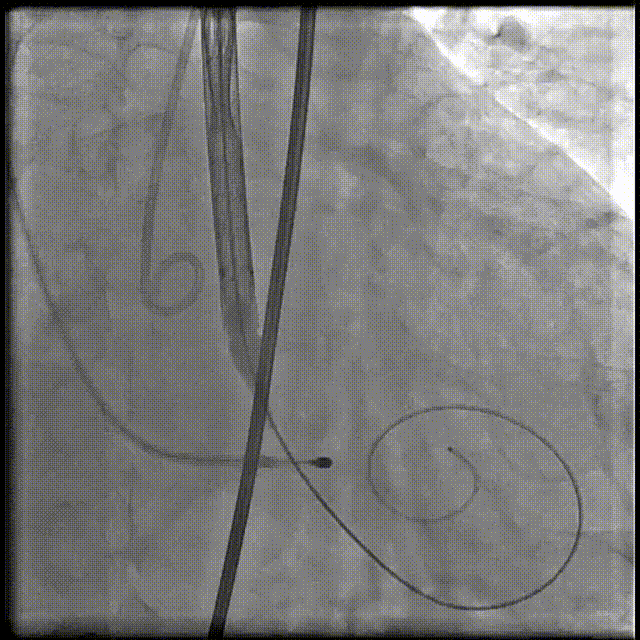

术中操作

手术影像

主动脉根部造影

输送器柔顺过弓、跨瓣

瓣膜开始定位

第一个瓣膜释放

植入第二个瓣

最终造影:无反流